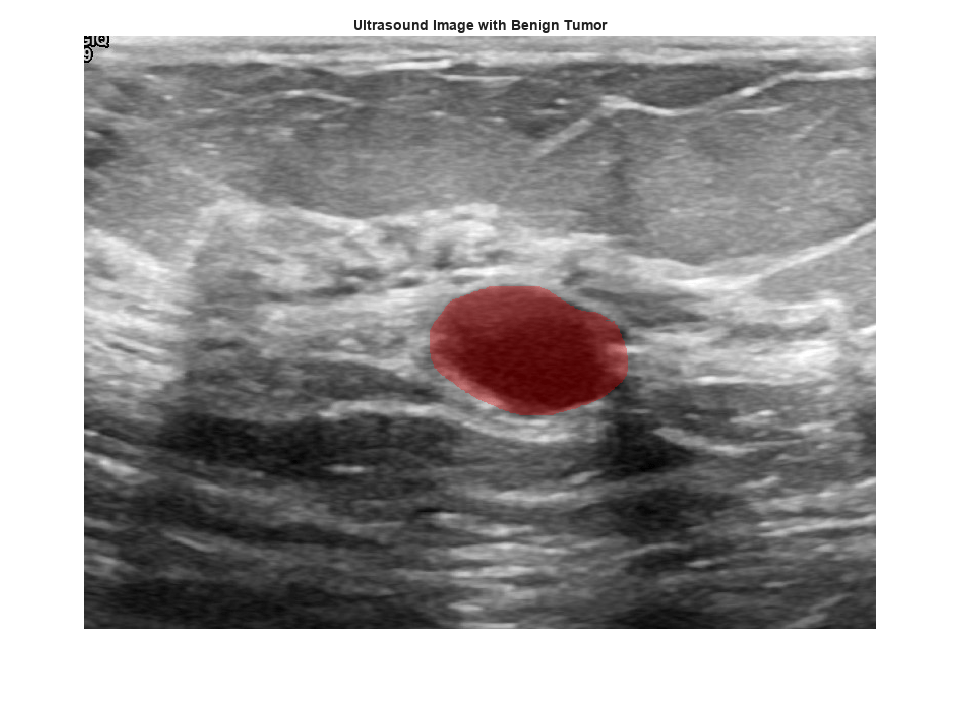

View an ultrasound image that contains a benign tumor with the tumor mask on the image.

benignIdx = find(imgds.Labels == "benign"); benignImage = readimage(imgds,benignIdx(146)); benignMask = readimage(maskds,benignIdx(146)); B = labeloverlay(benignImage,benignMask,Transparency=0.7,Colormap="hsv"); figure imshow(B) title("Ultrasound Image with Benign Tumor")